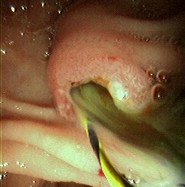

Can assist in the diagnosis of cholangitis by finding stones causing obstruction. Is also therapeutic, as the procedure can be used for biliary stone extraction. [Figure caption and citation for the preceding image starts]: Endoscopic retrograde cholangiopancreatography reveals a large common bile duct (CBD) stone (arrow) in the mid-common bile ductFrom the collection of Douglas G. Adler; used with permission [Citation ends].Endoscopic retrograde cholangiopancreatography reveals a large common bile duct (CBD) stone (arrow) in the mid-common bile duct[Figure caption and citation for the preceding image starts]: Endoscopic photo of same patient following removal of large common bile duct (CBD) stone; note copious pus draining through the ampullaFrom the collection of Douglas G. Adler; used with permission [Citation ends].Endoscopic photo of same patient following removal of large common bile duct (CBD) stone; note copious pus draining through the ampulla

direct observation of bile duct stone or other obstruction